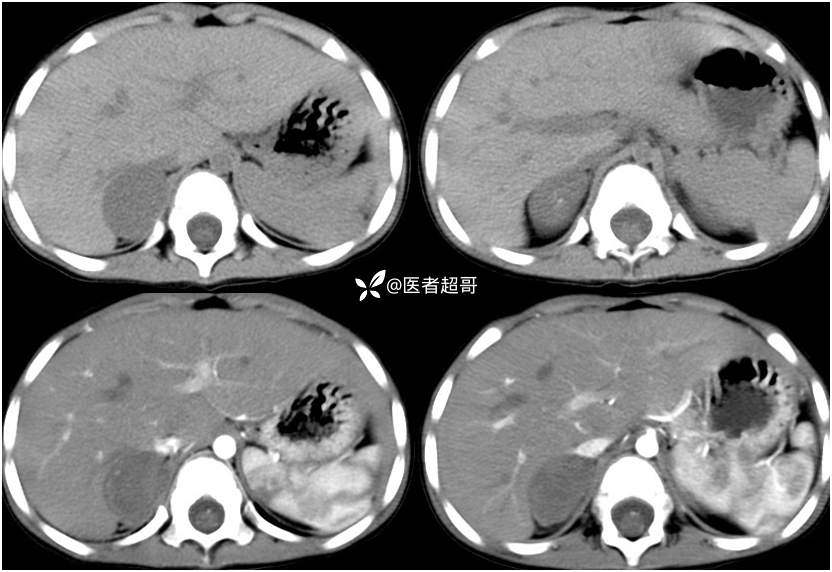

病例【影诊笔记713】男,3岁,发现肝占位入院?请诊断分析!